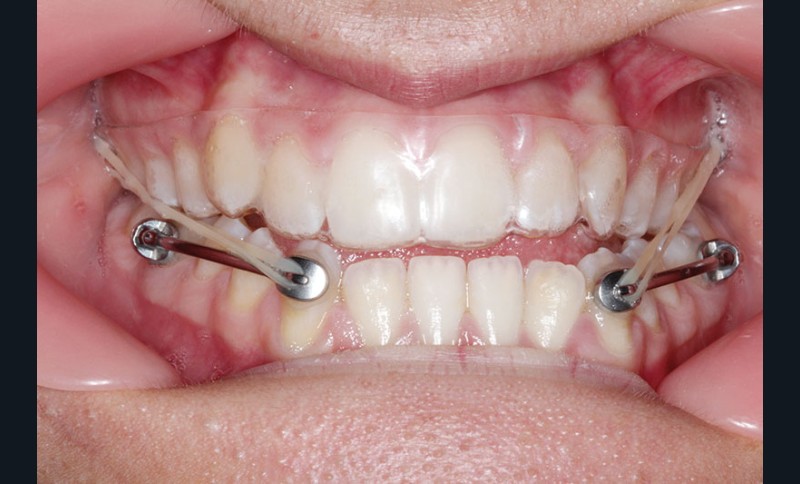

1re phase : recul des secteurs latéraux mandibulaires avec le Motion Classe III Carriere (fig. 4 à 6)

Nous mettons en place des bras latéraux Motion associés à des élastiques intermaxillaires ancrés sur des brackets sur 17 et 27 et une gouttière thermoformée maxillaire portée jour et nuit :

• 1er mois : élastiques 6 oz. 1/4”

• 2e mois et suivants : élastiques 6 oz.1/4“

L’objectif de cette étape est d’obtenir un recul des secteurs latéraux mandibulaires afin de positionner les molaires et canines en classe I et de réorienter le plan d’occlusion en haut en avant.